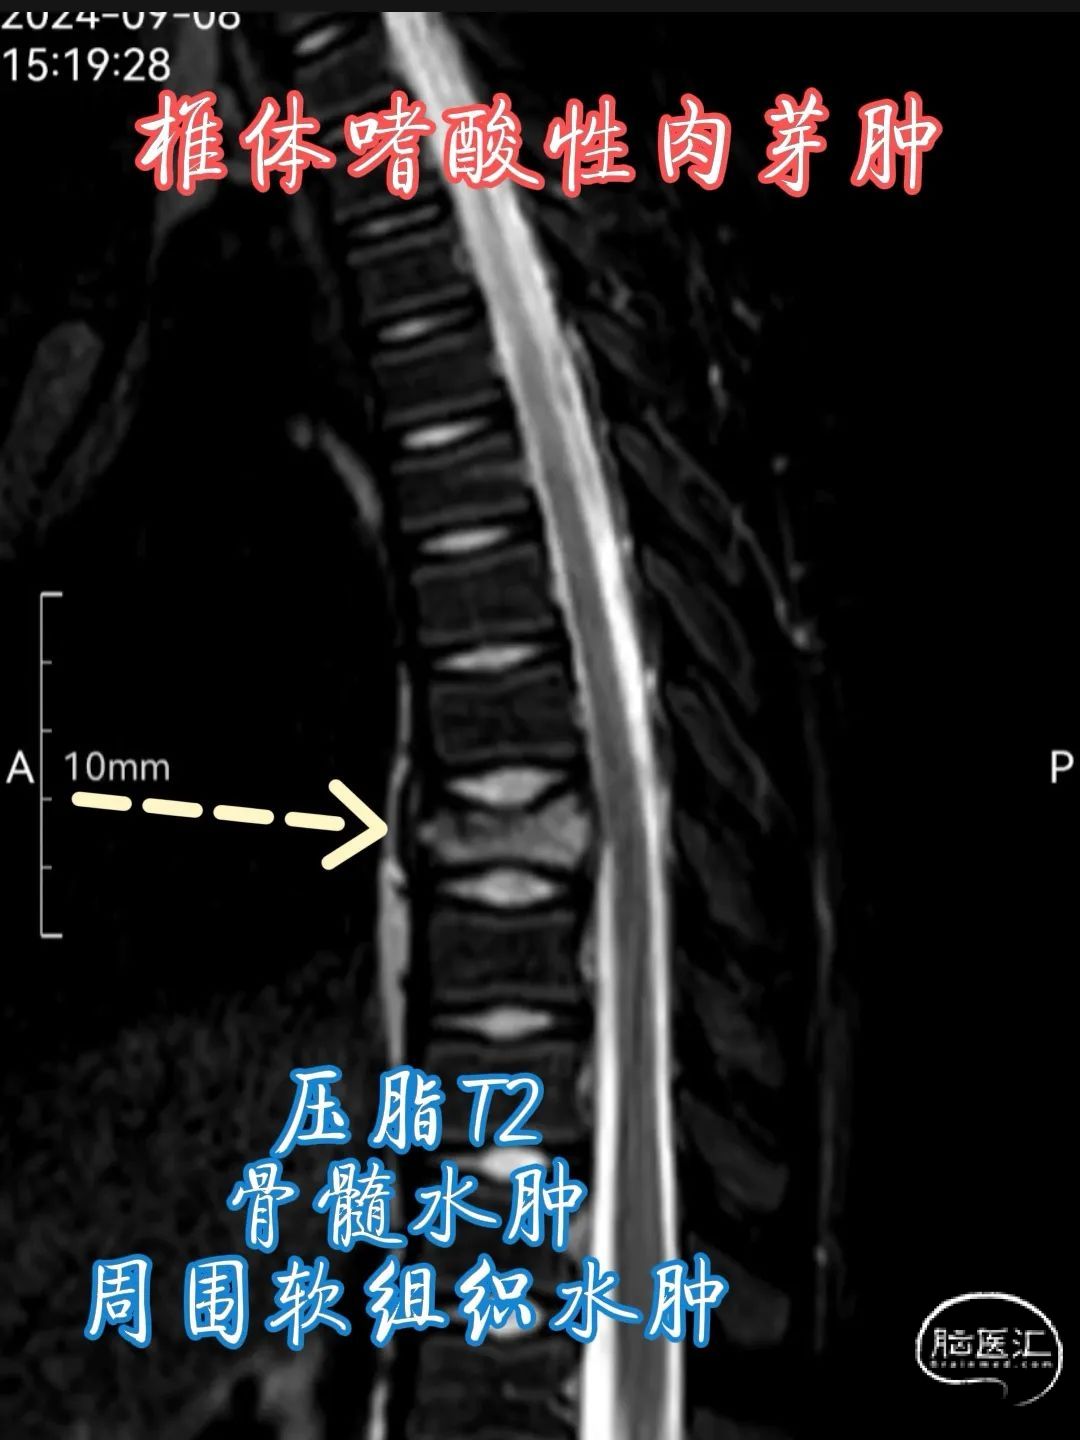

•MRI 检查 :MRI 对于检测椎体嗜酸性肉芽肿具有较高的敏感性,能够清晰地显示病变的范围、部位、形态以及与周围组织的关系。在 T1 加权像上,病变通常呈低到中等信号强度,与正常骨髓相比信号较低;在 T2 加权像上则呈高信号强度,这是由于病变组织内含有较多的水分和黏多糖等成分。此外,MRI 还可显示病变周围的软组织水肿、炎症反应以及神经受压等情况,对于判断病情和制定治疗计划具有重要价值。